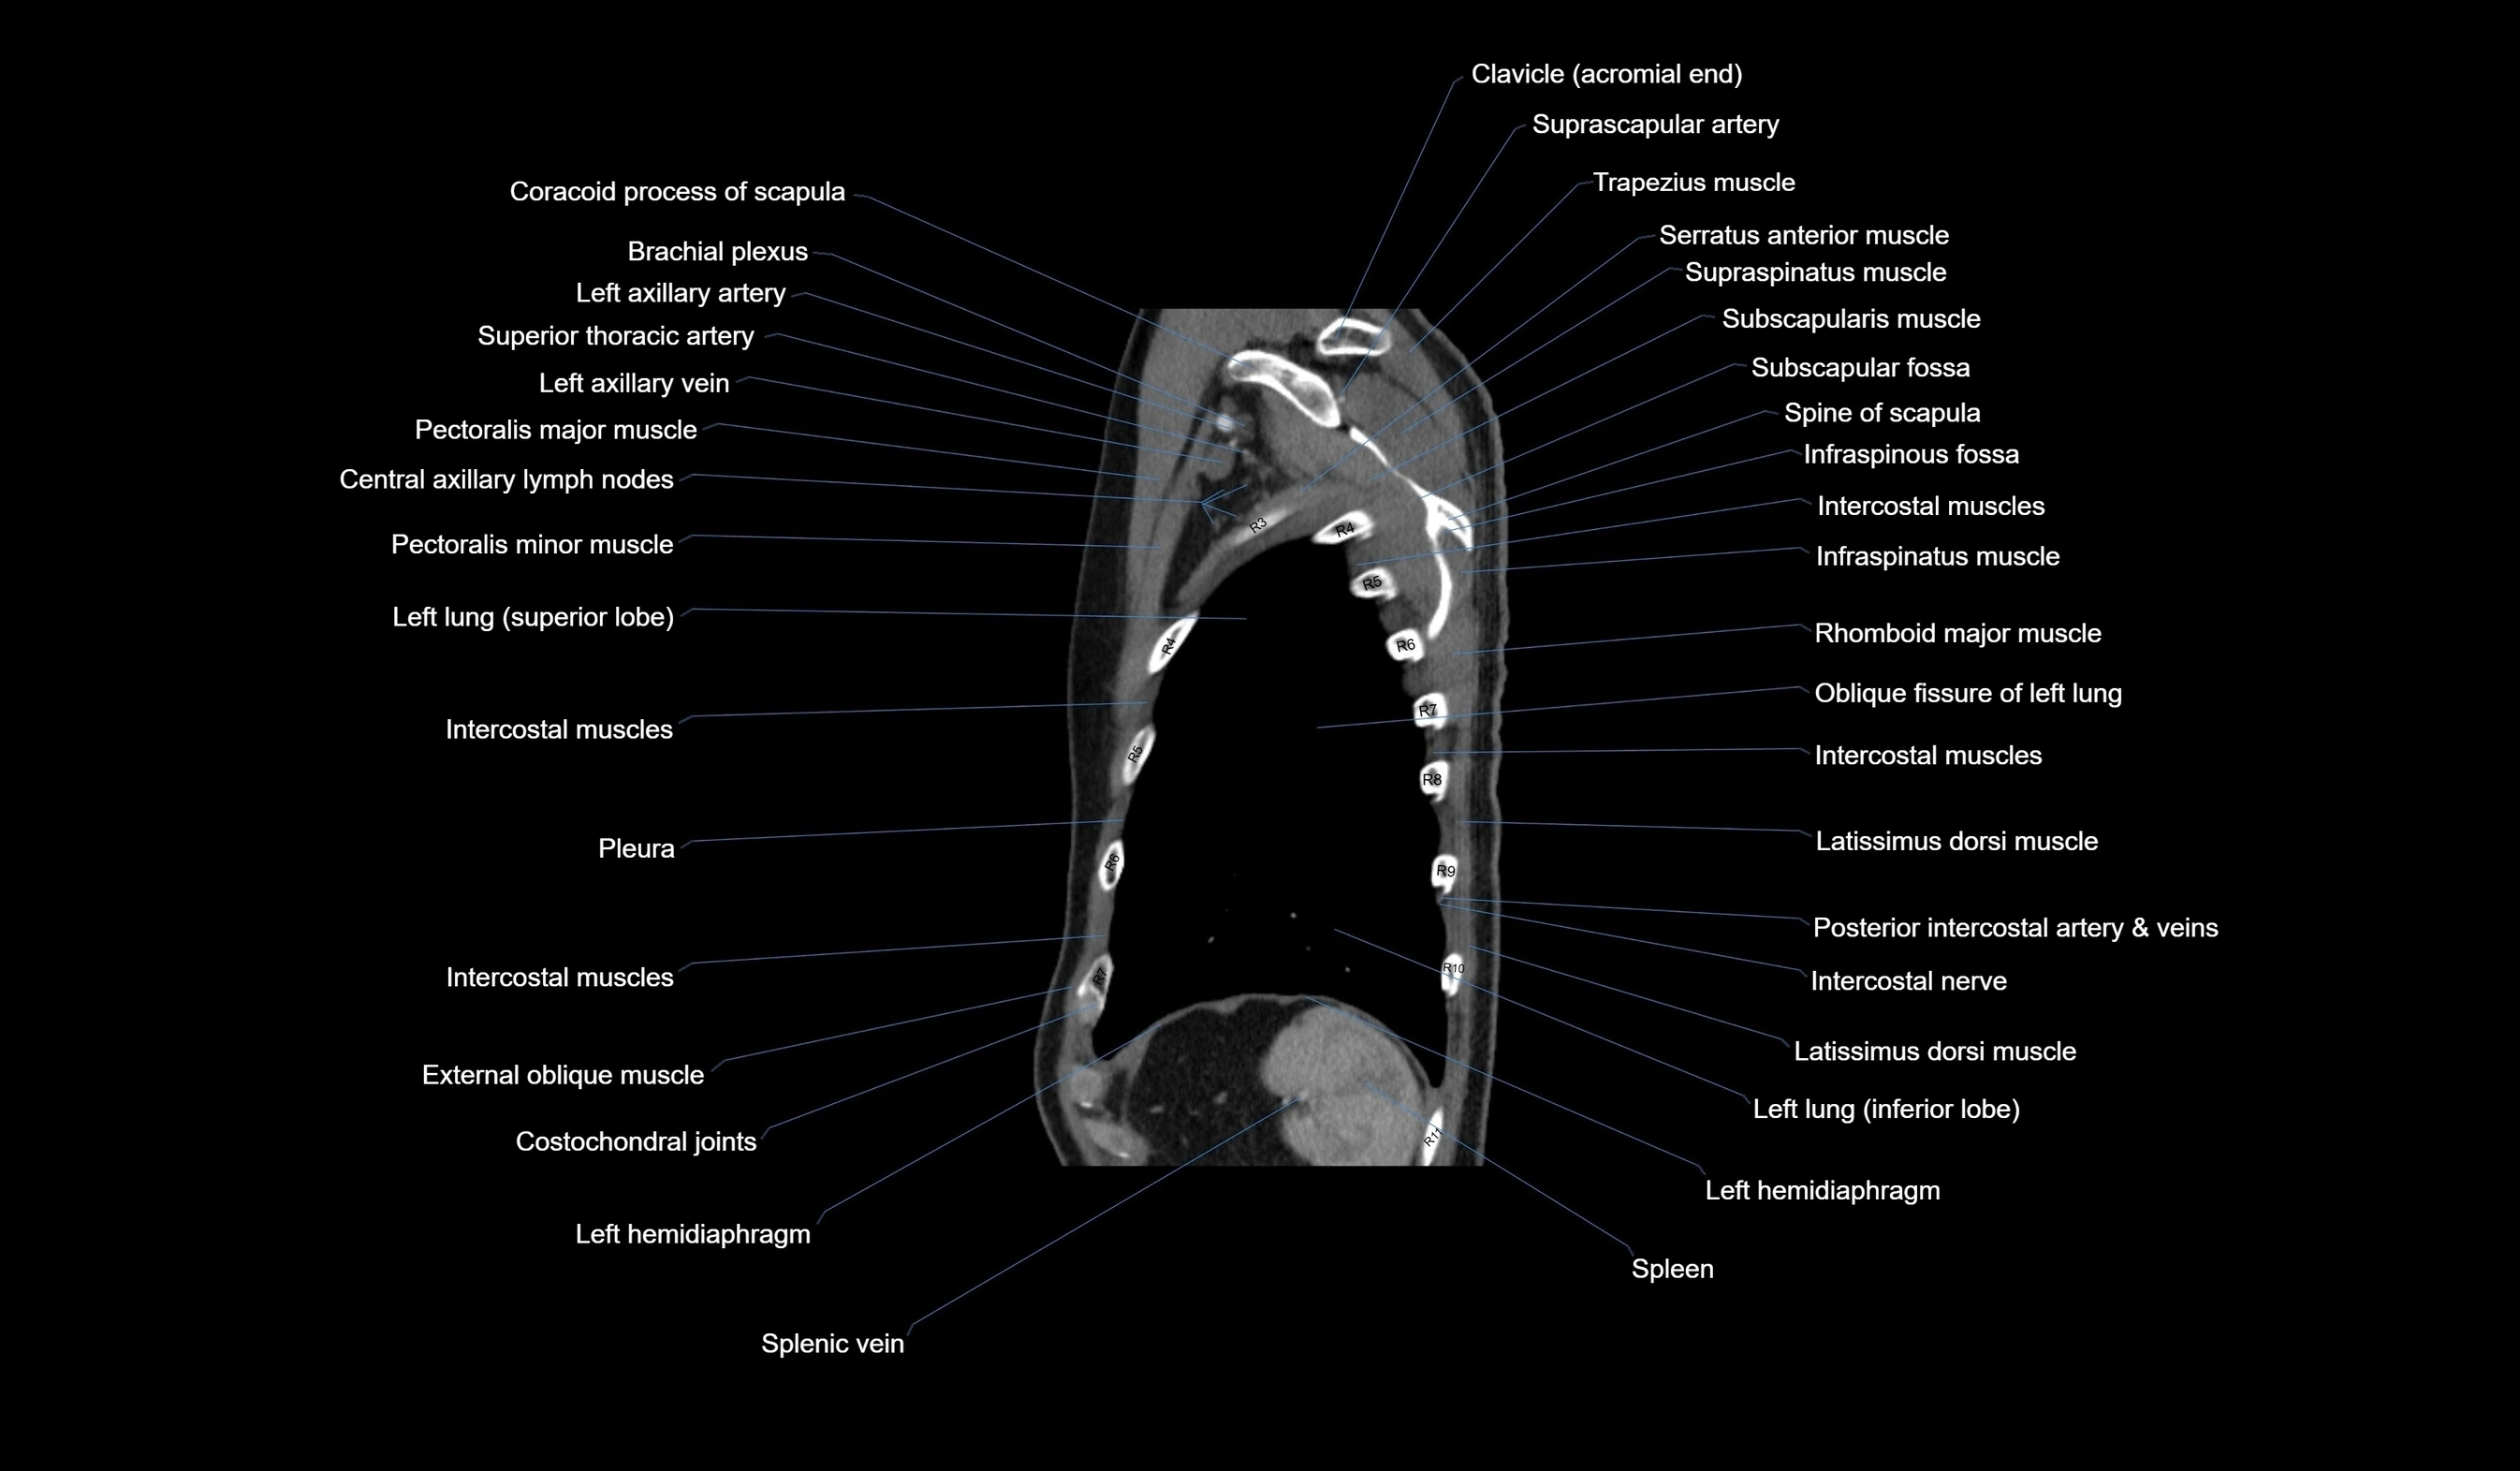

CT images